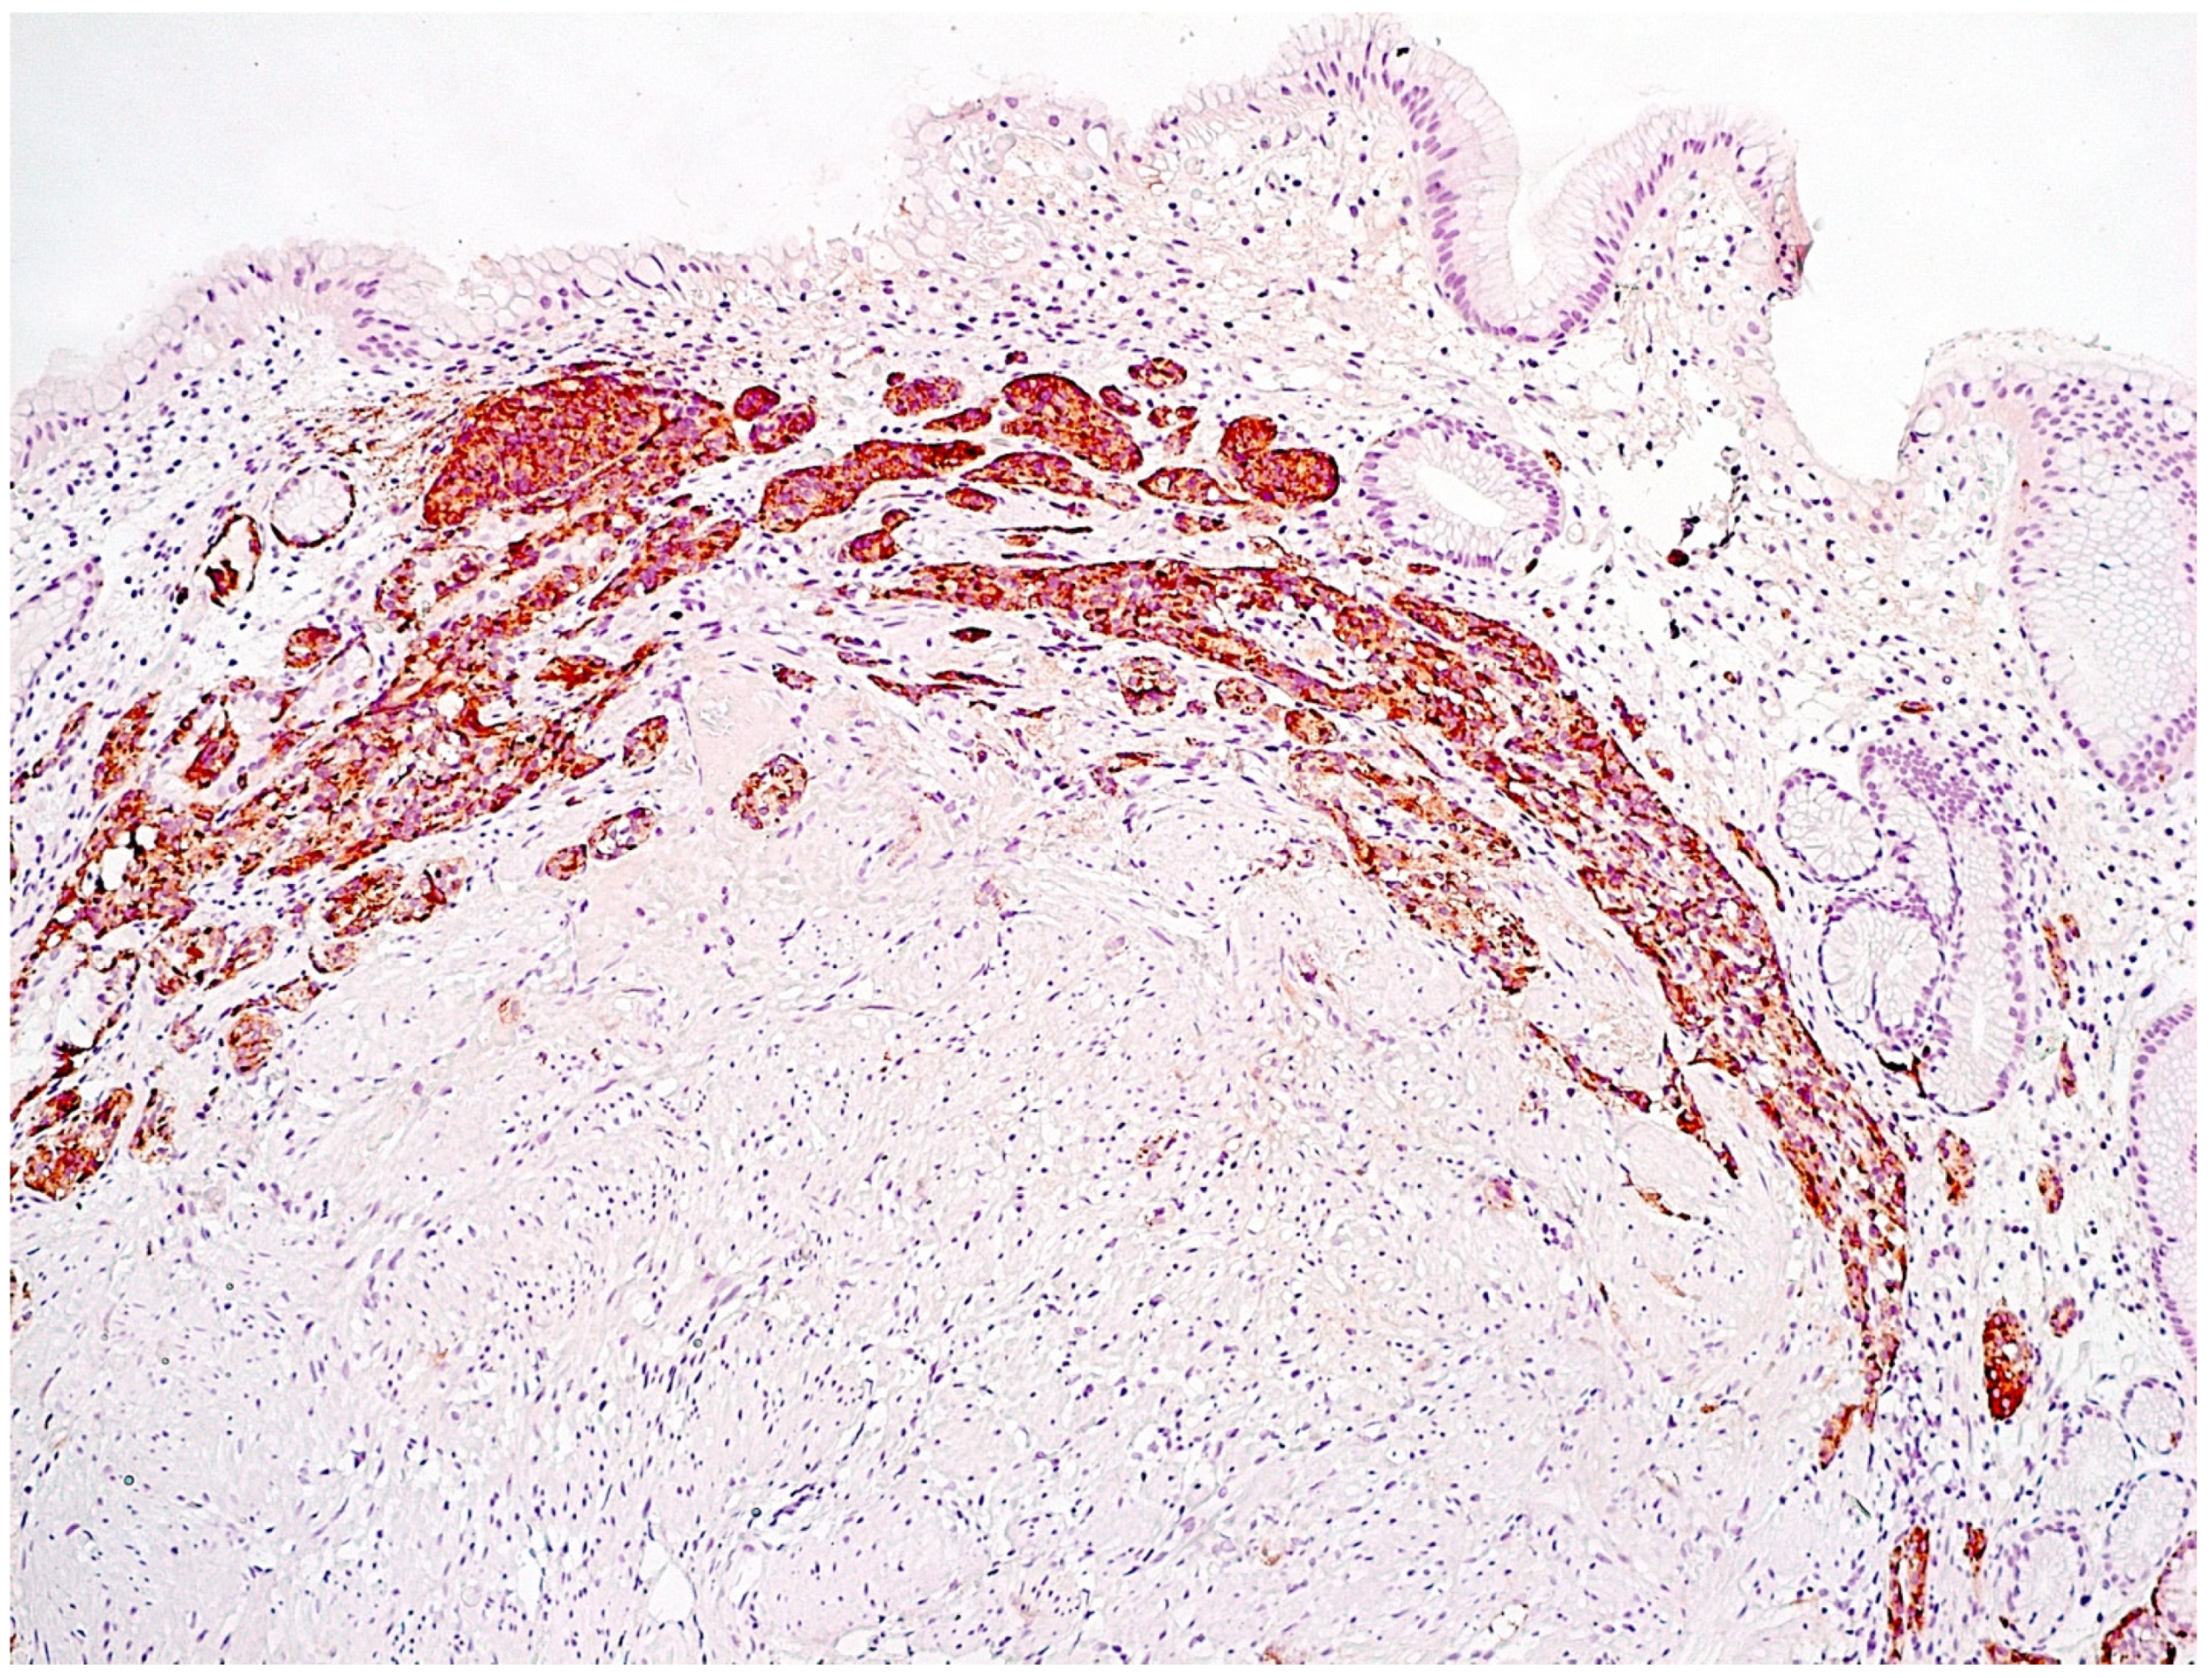

- Simple diffuse hyperplasia. This is characterized by a more than two-fold increase in the population of ECL cells. Diagnosis is difficult due to the lack of clear quantitative criteria. The diagnosis is poorly reproduced on biopsy material.

- Linear hyperplasia. The presence in one visual field of at least two groups of linearly located neuroendocrine cells, consisting of five or more cells. Usually, changes are diagnosed in the area of the neck glands (Figure 4).

- Micronodular hyperplasia. The presence of the cells’ cluster in contact with the basement membrane, but not exceeding the diameter of the gland, up to 150 μm in diameter, or a similar cluster located freely in the lamina propria of the mucous membrane.

- Adenomatous (adenomatoid) hyperplasia. The presence of an aggregate of five or more clusters (Figure 5).

- Neuroendocrine cells dysplasia. Merging clusters with diameters of more than 150 µm but less than 500 µm.